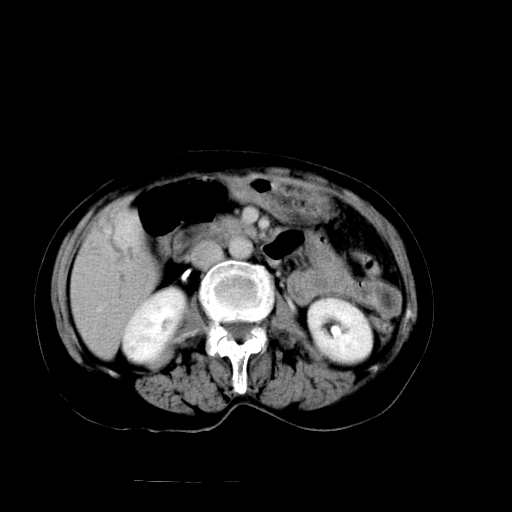

以下是引用随光逐影在2009-4-7 8:21:00的发言:[br]肝内外胆管多发性结石并肝内外胆管扩张;胆系感染。